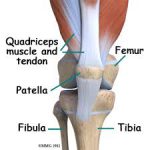

基本的な動きは曲げ伸ばしを行い、それに伴い回旋動作が入ります。

これをスクリューホームムーブメントという長い名前もついております。

膝をまっすぐにピンと伸ばすと安定性が増して、しゃがむ、立ち上がる時は大きく曲がります。

また膝の曲げ伸ばしの際には必ず軸運動が発生します。

この軸運動があることにより、曲げ伸ばしがきちんとできると言い換えることもできます。